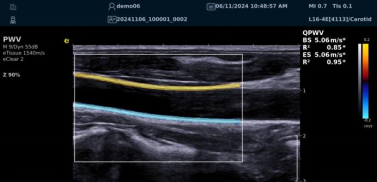

QPWV 彩色脉搏波传导速度定量技术

QPWV 技术是hjc888黄金城官网医疗的极速脉搏波速度测量技术,对脑卒中诊疗优势明显:

image.png

? 可进行动脉壁运动速度 - 时间彩色成像,直接测量单点脉搏波传导速度及相关参数(如 BSES 时的速度及标准差)。

? 能在血管内中膜增厚前的内皮功能不全阶段检测异常,对早期动脉硬化评估极具临床价值。

? 操作简单直接,无需附加设备,影响因素少,检测快速、重复性和稳定性高。